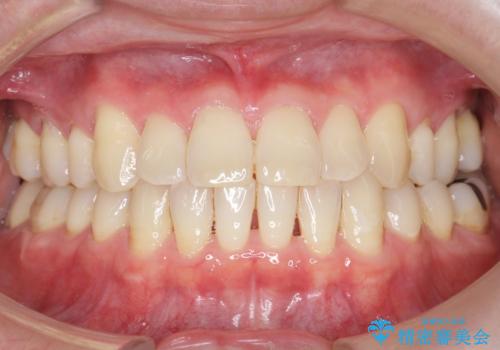

不適合な銀の詰め物とう蝕の除去により奥歯の違和感がなくなり、セラミック治療により機能性・審美性が向上し、患者様に喜んで頂けました。

被せ物の種類:右下6 e-max press セラミックインレー

右下7 メタルボンドクラウン エコノミー